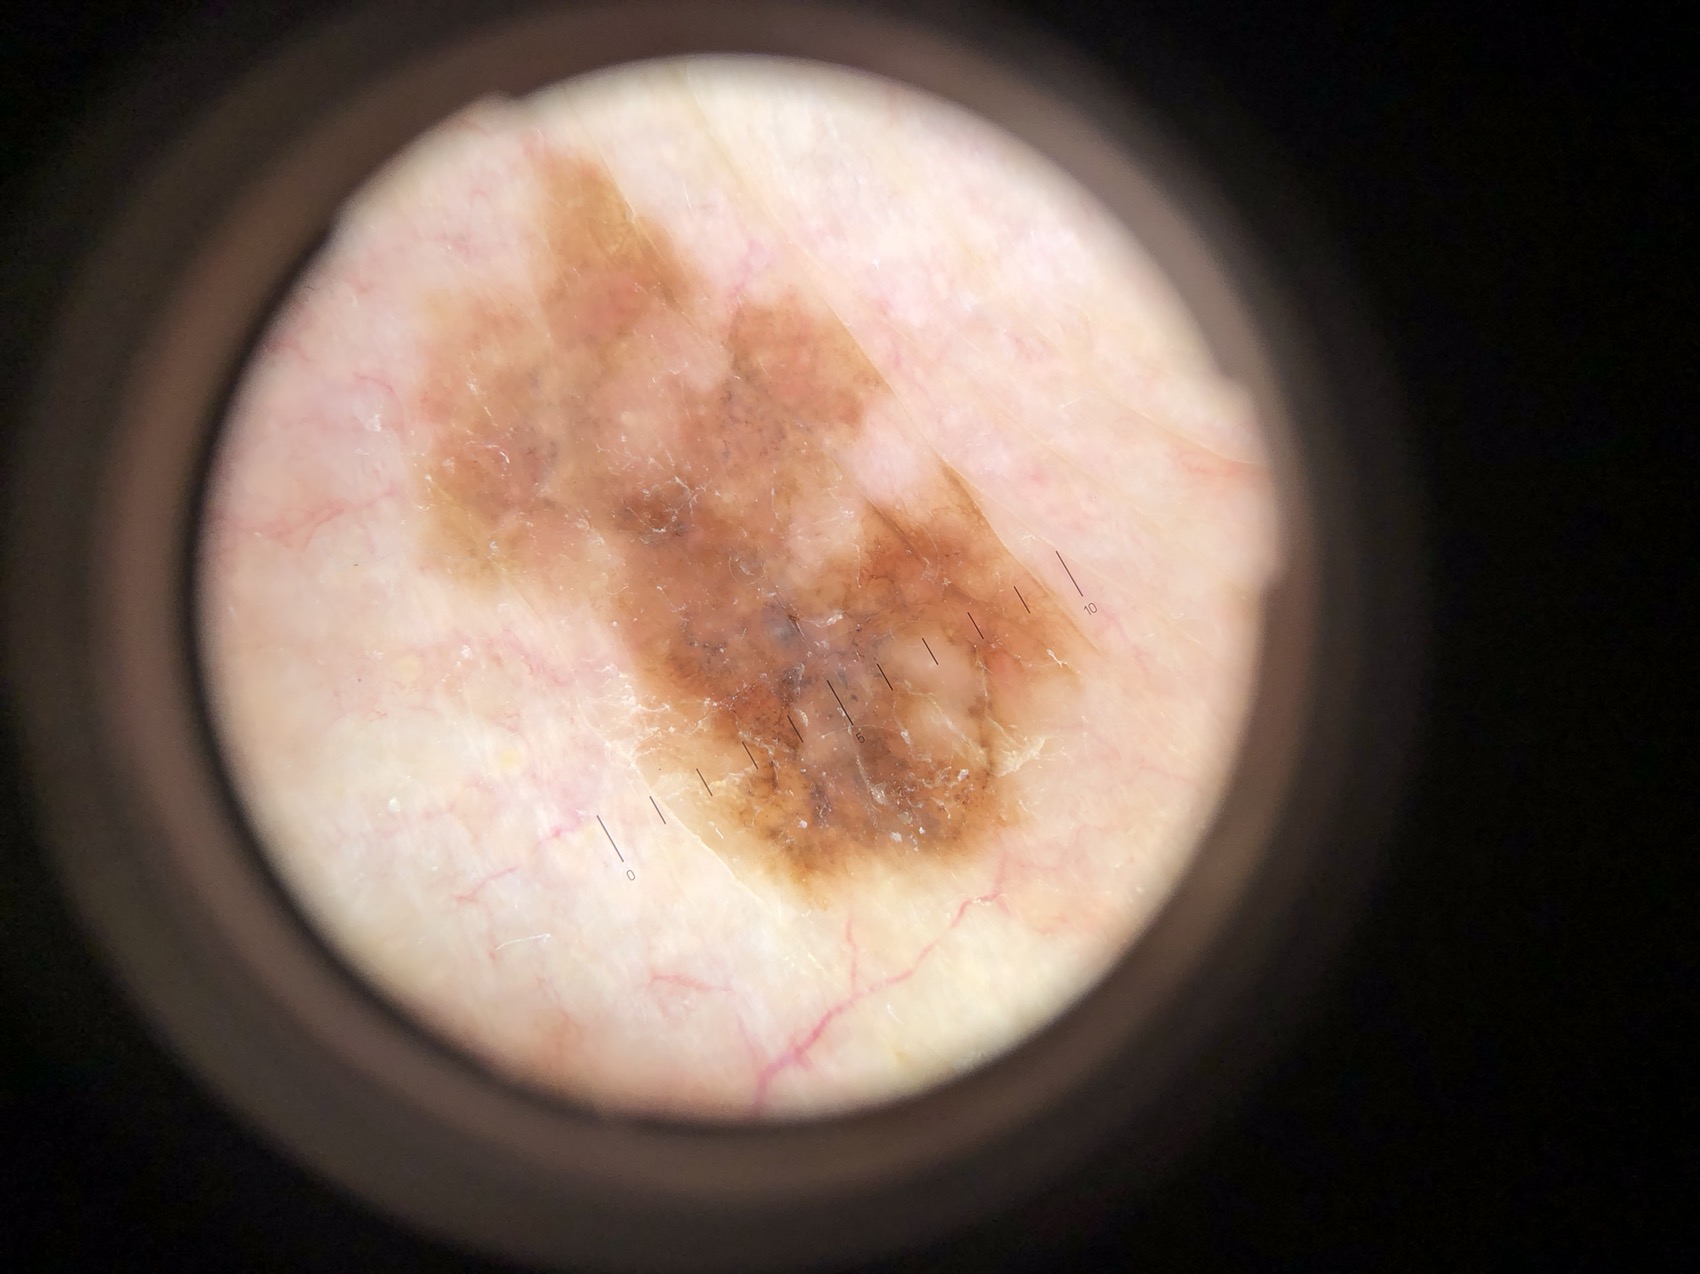

Seuraavana muutamia luomikuvia ja heti perään valokuva joka otettu dermatoskoopin kautta. Testaa itsesi jos tunnistat ko. muutokset!

Potilas 1, ohimolla lähes musta ihomuutos, vähän koholla:

Potilas 1: rasvasyylä ohimolla.